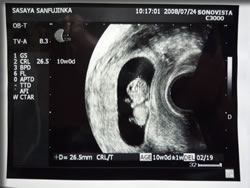

ついに超音波検査の写真をもらったのら。

しかも、超音波検査しているときのビデオまでもらったのら。

10週目

8月8日時点でのベビちゃんの大きさが 48mm。

それでも 心臓が動いてて、

もぞもぞ 動いてて、

手も足もはえてて、

すごい。